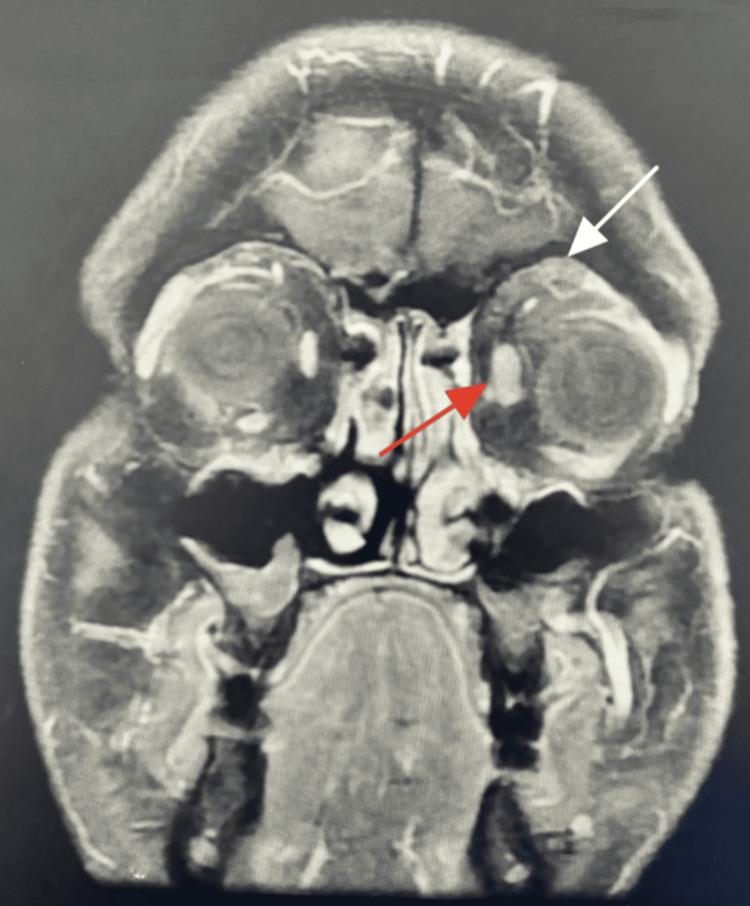

We present a rare and challenging case of a man who presented with mild mechanical ptosis and inferior dystopia, diagnosed with eyelid amyloidosis. A 40-year-old healthy man presented with a painless mass on his left upper eyelid that started one year ago. He noted that the mass increases in size when he eats meat, but there has been no overall progression over time. He experienced inferior dystopia with left upper eyelid fullness, swelling, and mild mechanical ptosis of the left eye. The measurements were as follows: marginal reflex distance 1 was 5 mm (oculus dexter, OD) and 4 mm (oculus sinister, OS); palpebral fissure height was 13 mm (OD) and 10 mm (OS); Hertel exophthalmometer reading at 105 was 22 mm (OD) and 23 mm (OS). CT was done with the impression of a dermoid cyst. It showed complex mass lesions of mixed fat, soft tissue, and calcification, predominantly involving the left upper eyelid with deeper extension into the superior compartment of the extraconal part of the fat of the orbit, close to the superior oblique levator muscle, with subsequent mild enlargement of the extraconal muscle group bilaterally, predominantly seen on the left side. The excisional biopsy showed amyloidosis. Amyloidosis is uncommon, progressive, and slowly associated with significant ocular morbidity. The diagnosis might be delayed because of an unusual presentation.